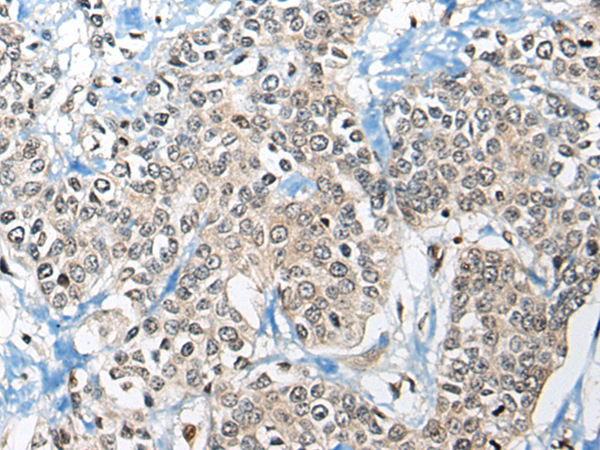

IHC positive control: |

Human prostate cancer |

IHC Recommend dilution: |

20-100 |